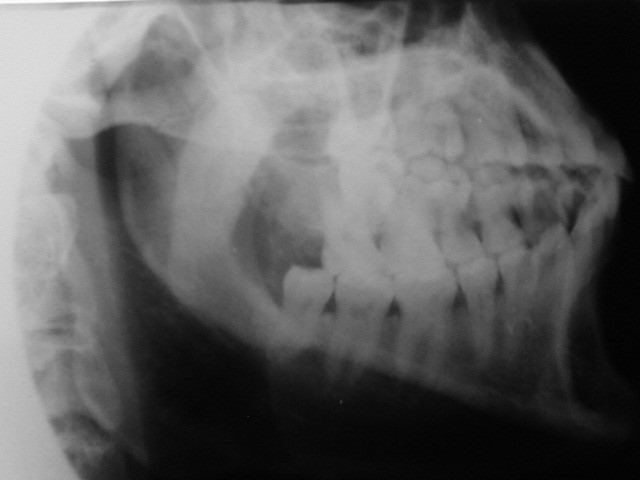

Proyección lateral oblicua Ap. del cuerpo y rama ascendente de la mandíbula, cóndilo y apófisis coronoides y sínfisis mentionana.